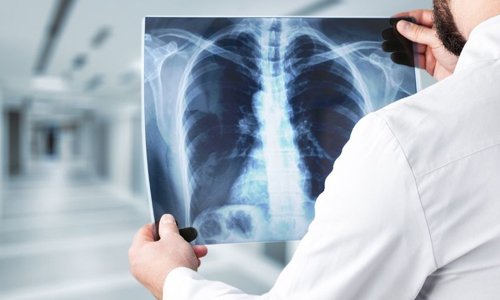

At Delta Imaging Clinic, we understand how important accurate diagnosis is in making informed medical decisions. That’s why we offer specialized Second Opinion Radiology Services, led by Dr. Krushna Gandhi, M.B.B.S, M.D (Radiology) — a trusted expert in diagnostic imaging.

Dr. Mrs. Krushna Chandak Gandhi is a distinguished professional known for her dedication and contribution in the field of Radiology. With a career spanning over 10+ years, she has earned a reputation for her commitment to excellence, compassion and thought leadership. She holds an MBBS and MD in Radiology and serves as a Visiting Radiologist. She is Expertise in Comprehensive interpretation of X-rays, ultrasound scans, color Doppler, and other diagnostic modalities.

I needed a chest X-ray done quickly for a visa medical, and Delta Imaging delivered. The process was fast, the equipment looked modern, and the staff were courteous. Dr. Gandhi even took the time to explain the results. Exceptional service!

Best center to get X ray and sonography done.Dr. Krushna Gandhi Mam Demonstrated with excellent communication skills, ensuring I understood the procedure and felt at ease throughout. The staff is very cooperative and the reports were quick 👍 …

Best center to get X ray and sonography done.Dr .krushna has a lot of experience and is expert in her own field.The staff is very cooperative and the reports were quick 👍 …

Best sonography and x-ray services in sakkardara. Only scannogram available here in east Nagpur.